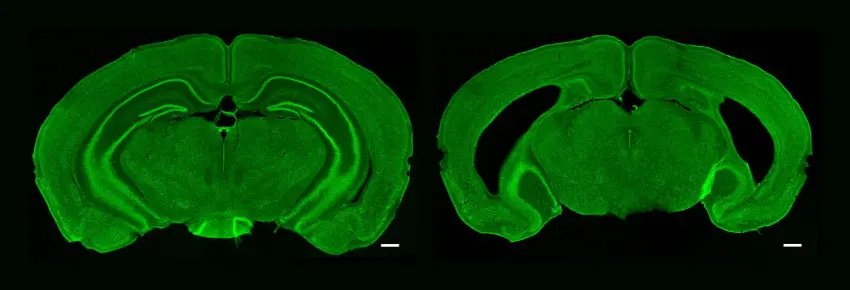

Due sezioni di ippocampo nel cervello di topo: a sinistra inalterato, e a destra significativamente ridotto. Fonte: Peter Finnie.

Ma i ricercatori volevano capire se e come l'ippocampo contribuisce a queste forme di memoria e plasticità corticale. Dopotutto, come altre forme di memoria che dipendono dall'ippocampo, la SRP interviene solo dopo un periodo di periodo di 'consolidamento', ad esempio nel sonno notturno. Per verificare se c'è un ruolo dell'ippocampo, hanno rimosso chimicamente grandi porzioni della struttura in un gruppo di topi e hanno cercato le differenze tra i gruppi nella risposta elettrica rivelatrice che dovrebbe evocare ogni tipo di memoria di riconoscimento.

I topi con o senza ippocampo sono andati ugualmente bene nell'apprendimento SRP (misurato non solo elettrofisiologicamente ma anche dal comportamento), suggerendo che l'ippocampo non era necessario per quella forma di memoria. Sembra sorgere, e anche consolidarsi, interamente all'interno della corteccia visiva.

Al contrario, i ricercatori hanno scoperto che non c'era la plasticità della sequenza visiva senza un ippocampo intatto. I topi senza la struttura non hanno mostrato alcuna risposta elettrica elevata alle sequenze durante i test, nessuna capacità di riconoscerle al rovescio o quando differite, e nessuna inclinazione a 'riempire lo spazio vuoto' quando mancava. Era come se la sequenza visiva, e perfino ogni immagine nella sequenza, non fosse familiare.